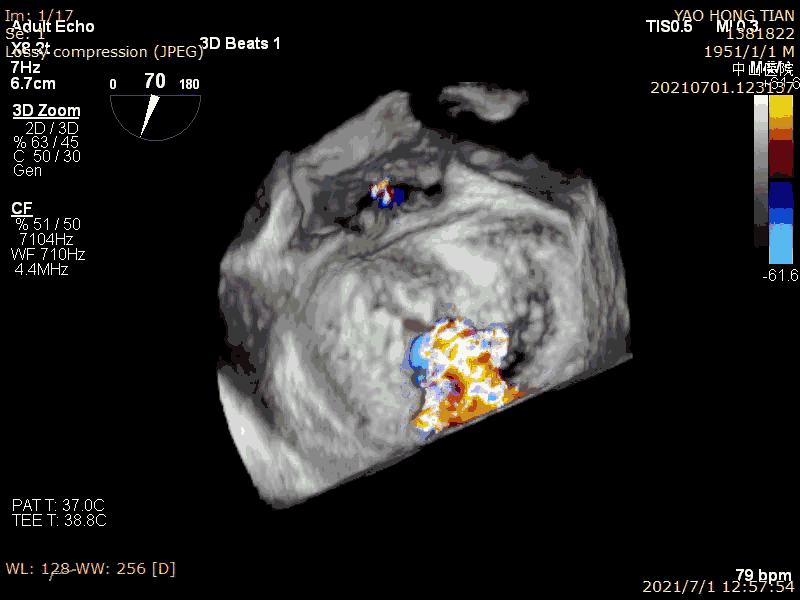

Patient: Male, 70 years old. Preoperative ultrasound diagnosis: Left ventricular ejection fraction (LVEF) 58%, left ventricular end-diastolic diameter (LVDD) 52mm, left atrial diameter (LAD) 57mm, pulmonary artery systolic pressure (PASP) 63mmHg. Severe mitral regurgitation caused by mitral valve leaflet malalignment, vena contracta (VC) 6*13mm, regurgitant area 19.8cm² (Figures 1-2).

Massive regurgitation at A2P2 caused by leaflet malalignment